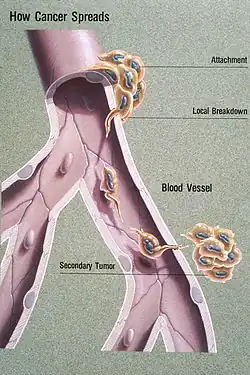

| Illustration showing hematogenous metastasis | |

Metastasis is the spread of a pathogenic agent from an initial or primary site to a different or secondary site within the host's body;[1] the term is typically used when referring to metastasis by a cancerous tumor.[2] The newly pathological sites, then, are metastases (mets).[3][4] It is generally distinguished from cancer invasion, which is the direct extension and penetration by cancer cells into neighboring tissues.[5]

Some cancer cells, known as circulating tumor cells (CTCs), are able to penetrate the walls of lymphatic or blood vessels, and circulate through the bloodstream to other sites and tissues in the body.[6] This process, known respectively as lymphatic or hematogenous spread, allows not only single cells but also groups of cells, or CTC clusters, to travel. Evidence suggests that CTC clusters may retain their multicellular configuration throughout metastasis, enhancing their ability to establish secondary tumors.[7] This perspective aligns with the cancer exodus hypothesis, which posits that maintaining this cluster structure contributes to a higher metastatic potential. Metastasis is one of the hallmarks of cancer, distinguishing it from benign tumors.[8] Most cancers can metastasize, although in varying degrees. Basal cell carcinoma for example rarely metastasizes.[8]

Metastasis involves a complex series of steps in which cancer cells leave the original tumor site and migrate to other parts of the body via the bloodstream, via the lymphatic system, or by direct extension. To do so, malignant cells break away from the primary tumor and attach to and degrade proteins that make up the surrounding extracellular matrix (ECM), which separates the tumor from adjoining tissues. By degrading these proteins, cancer cells are able to breach the ECM and escape. The location of the metastases is not always random, with different types of cancer tending to spread to particular organs and tissues at a rate that is higher than expected by statistical chance alone.[12] Breast cancer, for example, tends to metastasize to the bones and lungs. This specificity seems to be mediated by soluble signal molecules such as chemokines[13] and transforming growth factor beta.[14] The body resists metastasis by a variety of mechanisms through the actions of a class of proteins known as metastasis suppressors, of which about a dozen are known.[15]

All steps of the metastatic cascade involve a number of physical processes. Cell migration requires the generation of forces, and when cancer cells transmigrate through the vasculature, this requires physical gaps in the blood vessels to form.[18] Besides forces, the regulation of various types of cell-cell and cell-matrix adhesions is crucial during metastasis.